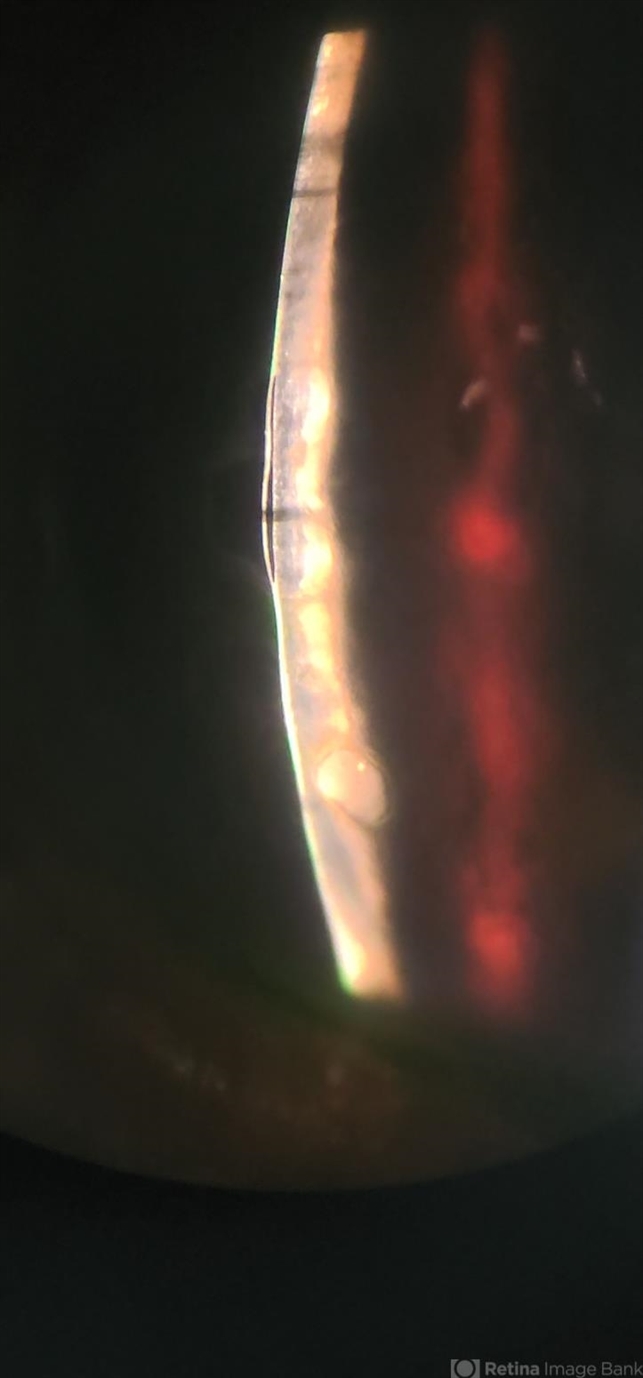

- corneal edema, bullous keratopathy

- smartphone photography through SLB

- Corneal Slit photograph of an 84-year-old man underwent uneventful cataract surgery 1 year ago elsewhere, with a multiple fluid filled Bullae, not responding on conservative management and planned for KP.